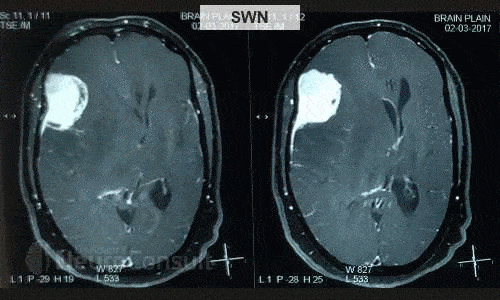

My Cases Studies & Work